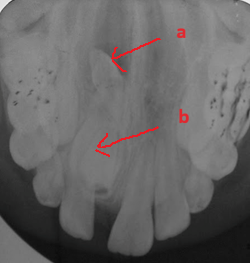

Khám lâm sàng thấy chậm mọc răng so với tuổi mọc dự kiến. Chẳng hạn như tuổi dự kiến mọc răng cửa giữa hàm trên vào khoảng 7-8 tuổi. Khi đến độ tuổi này nếu cả hai răng chưa mọc hoặc đã mọc một răng trong khi răng đối xứng chưa mọc hoặc mọc chậm thì nghi ngờ khả năng có răng thừa ngầm gây cản trở sự mọc răng. Hoặc phát hiện khe răng thưa răng cửa hàm trên hoặc có bất kì sự mọc lệch lạc nào của răng cửa hàm trên đều cũng nên chụp XQ kiểm tra sự hiện diện của răng thừa. Việc chẩn đoán bằng XQ là rất quan trọng. Tại BV Đa khoa Tỉnh Quảng Trị có đầy đủ các phương tiện chẩn đoán như XQ cận chóp, XQ răng toàn cảnh và đặc biệt là phương tiện chụp cắt lớp vi tính chùm tia hình nón (CT Cone Beam) có thể phát hiện răng thừa theo 3 chiều không gian mà các phương tiện khác có thể không phát hiện ra. Minh họa trường hợp cháu trai 8 tuổi sau đây là một ví dụ.

Răng thừa (b) mọc trong vòm miệng khiến cho R22 (a) mọc lệch xoay trục XQ răng toàn cảnh không thấy răng thừa do R21 (a) che khuất,(b) là R22 bị xoay trục

Hình ảnh răng thừa (a) xuất hiện rất rõ trên CT Cone Beam, (b) là hình ảnh R21

Hình 3: Tính ưu việt của CT Cone Beam trong chẩn đoán răng thừa

(Nguồn: Bệnh viện Đa khoa Tỉnh Quảng Trị)